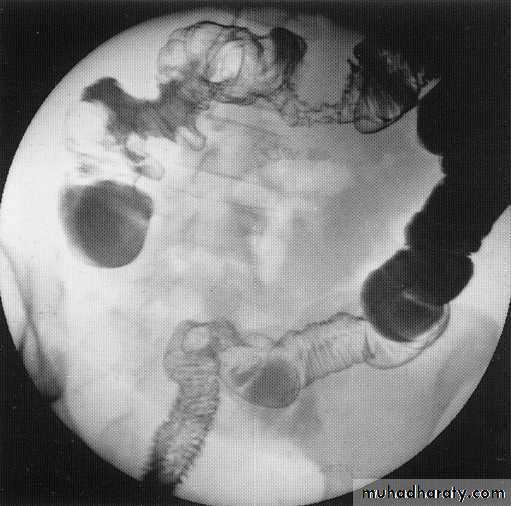

Small bowel contrast study

Barium follow throw x- rayCt scan with oral contrast

Ct scan with i.v contrast

Small bowel